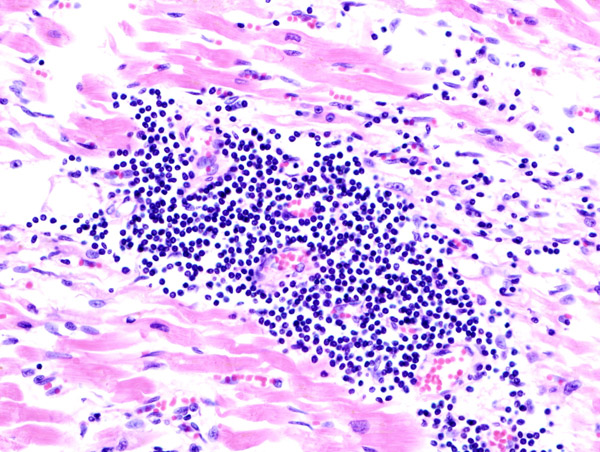

В некоторых случаях для подтверждения диагноза и выявления причины заболевания может потребоваться эндомиокардиальная биопсия.